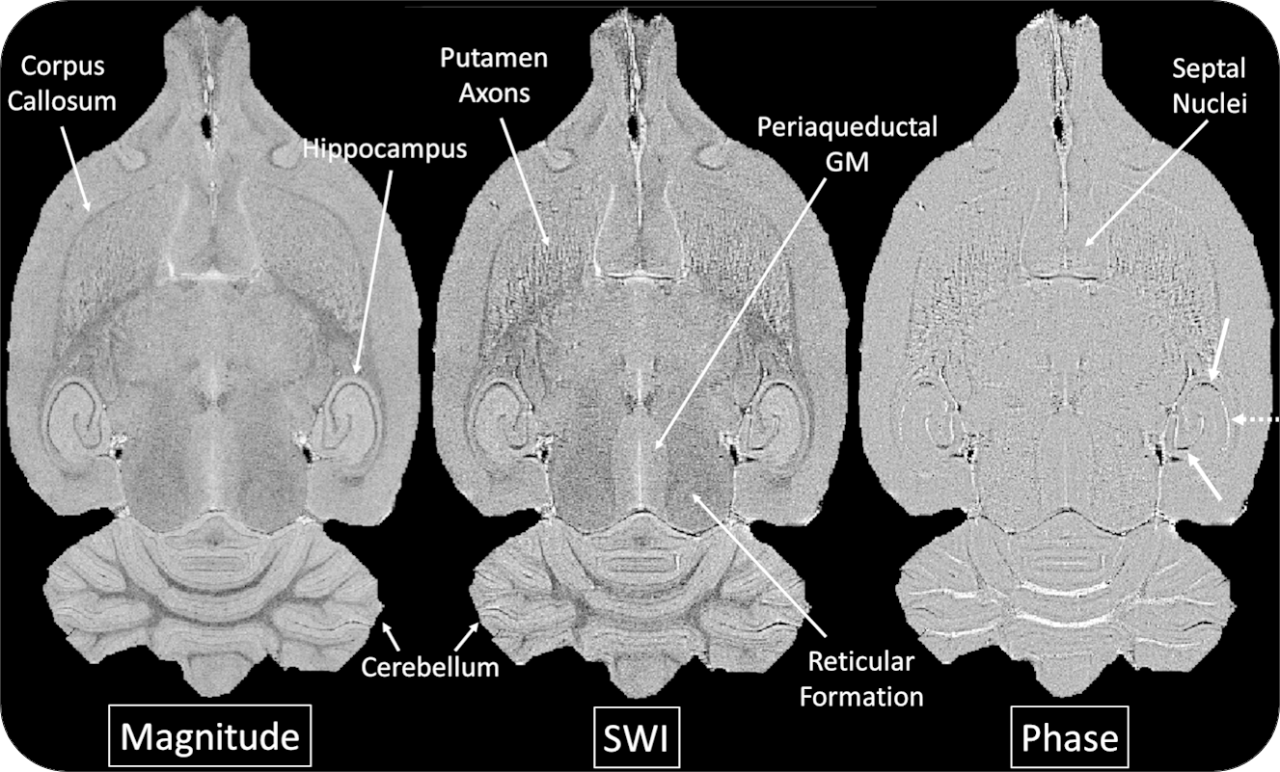

The ultra-high field of the BioSpec 152/11 provides extreme sensitivity for greatest resolution. Its streamlined design for mice studies makes handling simple, while its powerful software guarantees best results. It can be equipped with the MRI CryoProbe to increase sensitivity even further and together with the gradient strength of up to 1000 mT/m, highest resolution is achieved. It is built with nitrogen-free Ultra Shielded and helium Refrigerated (US/R) magnet technology for long service intervals

• Crisp and highly resolved images with native gradient strength of 740 mT/m, upgradable to 1000 mT/m

• MRI CryoProbe for exceptional increase in sensitivity